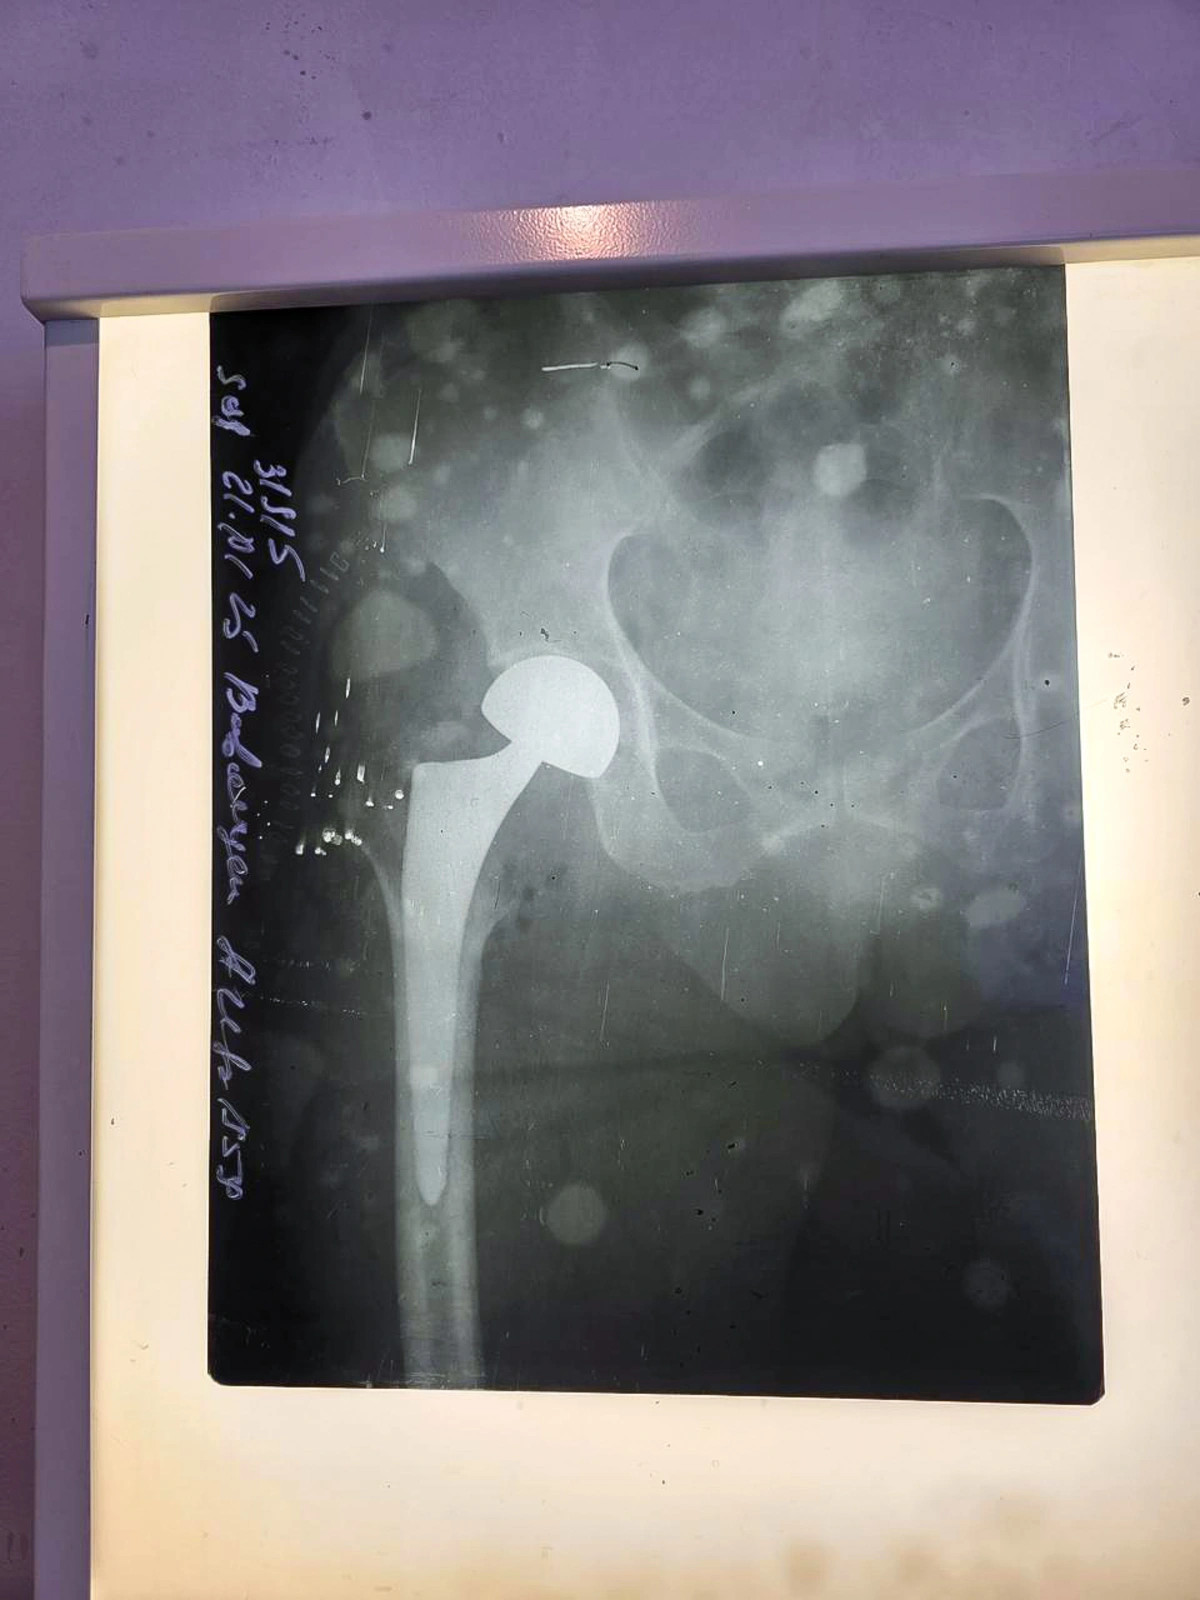

Sabunçu Tibb Mərkəzində endoprotez əməliyyatlarının (zədələnmiş və ya xəstə oynağın süni protezlə əvəz olunması əməliyyatı) icrasına başlanılıb.

Bildirilib ki, tibb mərkəzində ilk dəfə 66 yaşlı pasiyent üzərində həyata keçirilmiş endoprotez əməliyyatı uğurla başa çatıb.

Qeyd edək ki, endoprotez əməliyyatı zədələnmə, degenerativ və iltihabi xəstəliklər nəticəsində oynaqlarda yaranan dəyişikliklərin konservativ müalicə metodları ilə aradan qaldırıla bilmədiyi hallarda oynaqların tam və ya qismən süni protezlə əvəz olunmasıdır.